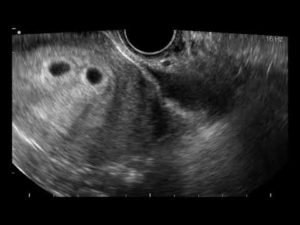

При двойне врач считает количество плодных яиц. Если каждый зародыш находится в своем округлом темном пятне, то врач делает вывод о наличии в утробе двойняшек. Если на снимке видно, что два эмбриона находятся в общем яйце, то ожидается рождение однояйцевых близнецов.

Фото УЗИ двойни на ранних сроках беременности, 8 недель

В 8 акушерских недель (или 6 недель от момента зачатия) обычно используют трансвагинальный способ УЗИ. Аппарат вводят внутрь, чтобы лучше разглядеть эмбрионы. На мониторе видны два или три темных пятна. Врач измеряет длину зародышей и фиксирует несколько сердцебиений.

В отличие от осмотра врача, двойня на УЗИ определяется с почти стопроцентной вероятностью. На экране она смотрится как два темных овала в матке.